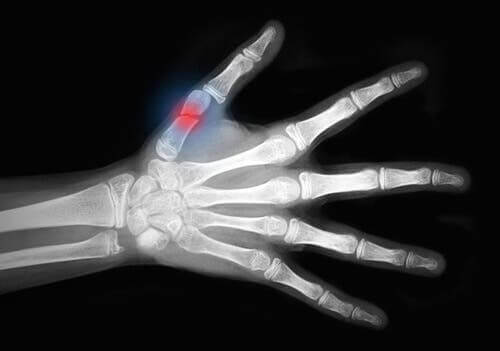

Op medisch gebied zijn huidavulsies traumatische verwondingen die de zachte weefsels van de huid over grote gebieden scheuren en het bot blootleggen. Ze hebben voornamelijk betrekking op de ledematen.